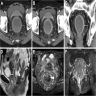

Radiology description

• Findings are largely nonspecific

• Computed tomography (CT) and magnetic resonance imaging (MRI) scans will demonstrate findings consistent with intestinal discontinuity, such as an ileostomy, colostomy or a colonic pouch

• Affected colonic segments may show fat stranding, wall thickening and fluid distension

• Target or water halo sign may be present, which is suggestive of inflamed colonic mucosa and edematous submucosa

• Reference: Insights Imaging 2019;10:41

Radiology images

Images hosted on other servers:

Postcolectomy CT and MRI